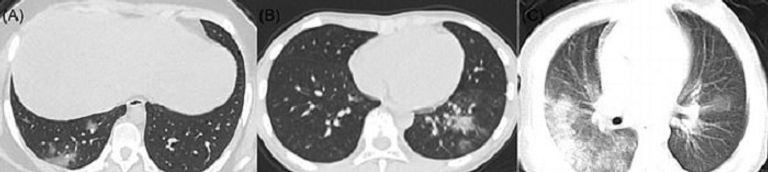

حذر أطباء نشروا أشعة مقطعية لأطفال بعد إصابتهم بفيروس كورونا المستجد من أن المرضى يمكن أن يعانوا تلفًا بالرئة.

وذكرت صحيفة "ديلي ميل" البريطانية أن فريقا من مستشفى أطفال بوسطن قيموا أشعة مقطعية لحالات إصابة من الأطفال بـ"كوفيد-19" لتحديد أبرز السمات المشتركة.

وفي دراسة على 20 طفلًا، كان نحو الثلثين لديهم ما يسمى بـ"عتامة الزجاج المطحون"، وهو مؤشر على انتشار الالتهابات.

وكان لدى نصف ما يعرف باسم "علامة الهالة"، التي تحدث عندما تحاوط الالتهابات كتلة، تعرف باسم "التصلد"، صعوبة في التنفس.

وقارن الأطباء بقيادة إخصائية الأشعة ألكسندرا فوست، الضرر جراء "كوفيد-19" مقابل أمراض أخرى تصيب الجهاز التنفسي، مثل: سارس، وميرس.

وجمعت فوست وزملاؤها 5 دراسات وأشاروا لأبرز التغييرات الملحوظة في رئة الأطفال، ونشروا نتائجهم في دورية " American Journal of Roentgenology".

وفحصت دراسة واحدة بمدينة ووهان الصينية 20 مريضًا مصابين بفيروس كورونا المستجد بمستشفى للأطفال أعمارهم ما بين يوم واحد و14 يومًا، و13 منهم كانوا ذكورا.

وكان جميع المرضى يعانون من تضرر جزء من الأنسجة أو تغيرت بشكل غير طبيعي في جدار الرئة، وكان النصف يعاني من تضررات ثنائية بالرئتين، بينما 30% كان الضرر برئة واحدة.

وكان 6 من بين 10 مرضى يعانون "عتامة الزجاج المطحون"، وهي سحابة ضبابية على الرئتين تشير لمجموعة مختلفة من المشاكل.

ويمكن أن تعني تلك السحابة أن الرئتين مملوءتان جزئيًا بمادة ملتهبة، أو أن هناك سماكة في أنسجة الرئة، أو انهيار جزئي للحويصلات الرئوية، وهي الأكياس الهوائية الموجودة بالرئتين.

وكان النصف يعانون من "التصلد"، وهو امتلاء الأكياس الهوائية في الرئتين بمواد عادة ما تكون دماء أو مياها أو صديدا.

وبعد العلاج، خضع 6 أطفال لأشعة مقطعية، وتبين أن حالات "التصلد" خفت تدريجيًا في 3 حالات.

ووجدت دراسة أصغر لـ5 مرضى صغار مصابين بفيروس كورونا المستجد حالة معتدلة من "عتامة الزجاج المطحون" بين 3 مرضى، لكنها شفيت مع الوقت.